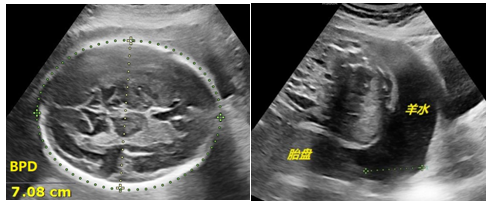

孕28-34周:TA继续生长发育,变得强壮有力。孕32周之后的TA 已经没有足够的空间畅游了,四肢也蜷曲起来,动作幅度也变小,胎位较为固定,也导致超声检查变得困难。尽管如此,我们依然通过超声关注两个方面(图7 ):一,TA的大小合适吗?晚孕期的TA逐渐展示出个体差异性,变得不那么“标准”,如有的腿短一些,有的头大一点,有的又太胖了。我们在超声下测评TA的各项数据是否符合标准孕周,如果实际孕周与标准孕周相差在两周以内也是允许的。二,TA赖以生存的附属三件套(胎盘脐带羊水)是否正常?胎盘是否成熟或老化?脐带血流是否正常?羊水量多还是少?当然除了超声,临床医生也会结合其他检查综合评估胎儿在母体的情况。

图7 超声显示晚孕

孕37-40周:TA已足月。超声下判断TA的胎位可谓轻而易举,瞬间确定。TA的各种系统器官已经发育成熟,头身长大缓慢、主打“养膘”。我们在超声下测量TA的双顶径、头围、股骨、腹围等各项参数,用以估算出TA的体重。我们通过超声观察TA的附属三件套的变化。羊水量逐渐变少。缺乏了羊水的映衬,超声对TA的显示愈发困难和模糊了(图8:超声显示晚孕足月)。

图8 超声显示:晚孕足月